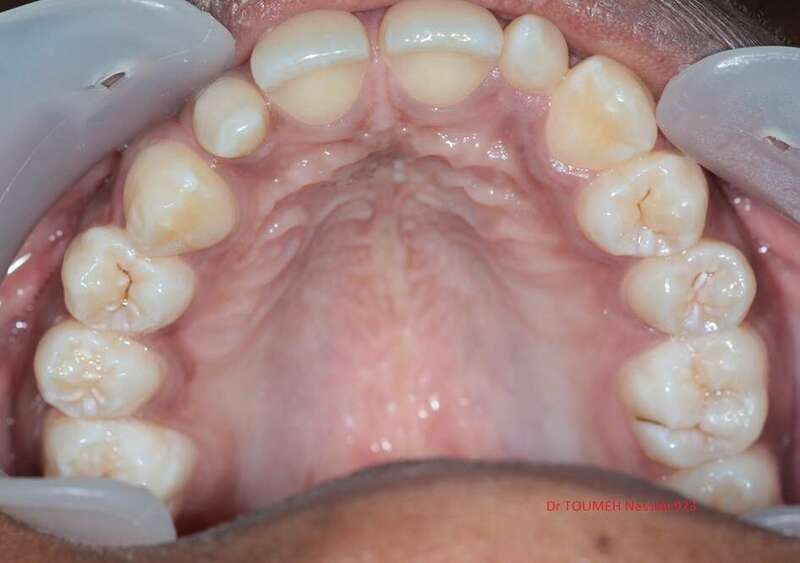

Latérales naines et orthodontie

la forme des dents influence grandement l’esthétique du sourire

La malformation des incisives latérales en est l'illustration

Le traitement consiste à redresser les dents à l'aide d'un appareil orthodontique (Multiattaches) et à redonner une forme normale aux dents malformées.

Dans ce cas présenté des couronnes provisoires en résines ont été posées.

Avant